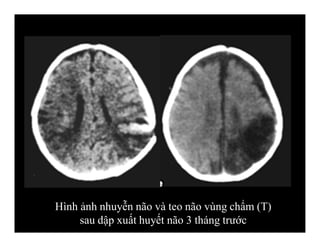

-Nhuyễn não (encephalomalacia)

-Teo não (atrophy)

DI CHỨNG CHẤN THƯƠNG SỌ NÃO

Hình ảnh nhuyễn não và teo não vùng chẩm (T)

sau dập xuất huyết não 3 tháng trước

Hình ảnh nhuyễnnão và teo não vùng chẩm (T) sau dập xuất huyết não 3 tháng trước